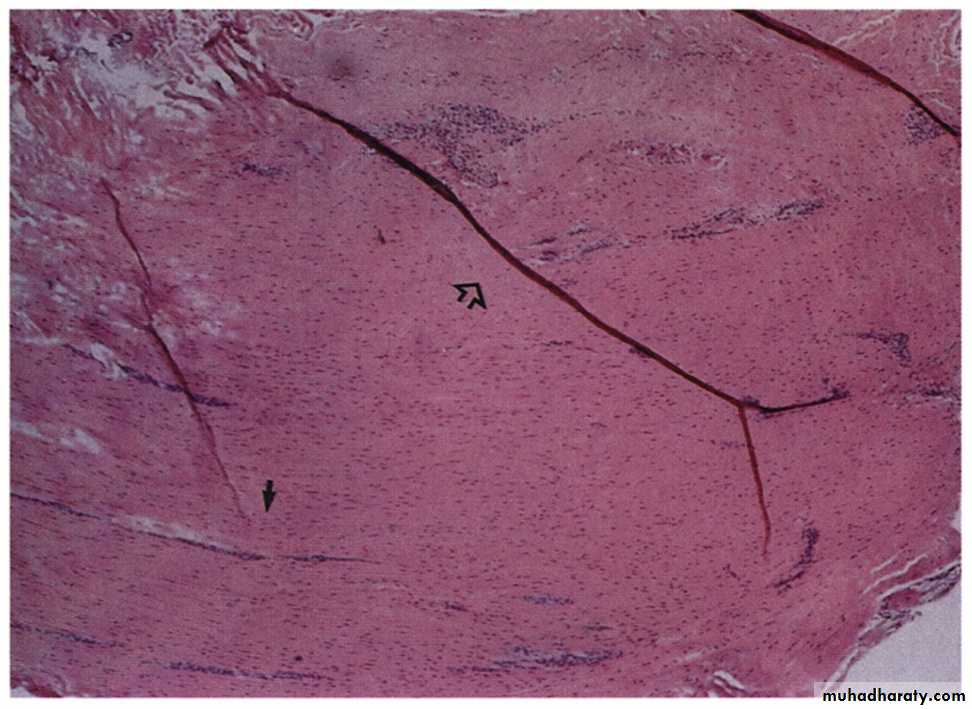

Tendinosis

Mucoid degenerationLoss of collagen tight bundled structure

FibrosisNeo-vascularisation

(Khan et al. 1999)